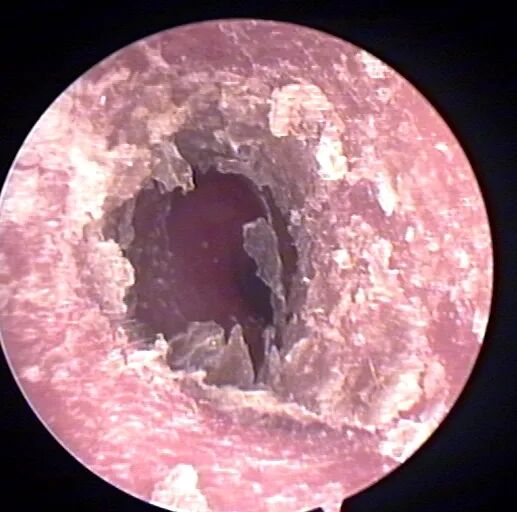

涂药时也不需要涂太多,薄薄一层就好,避免出现闷堵感,如